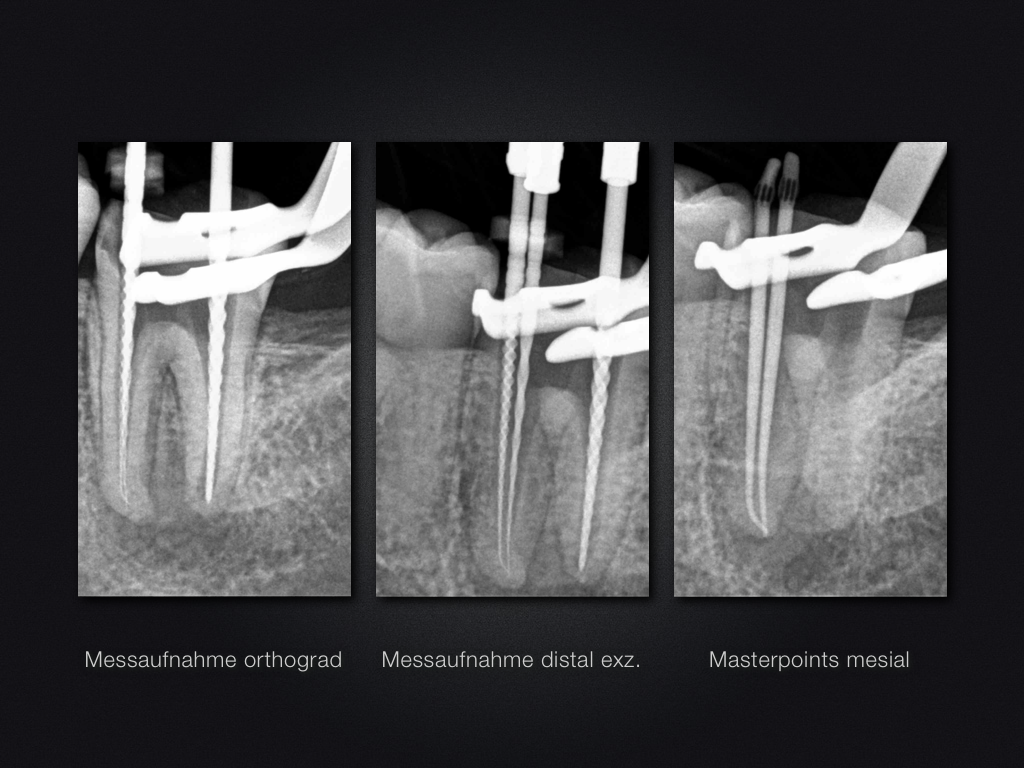

37D.010

2D vs. 3D (XXIV)